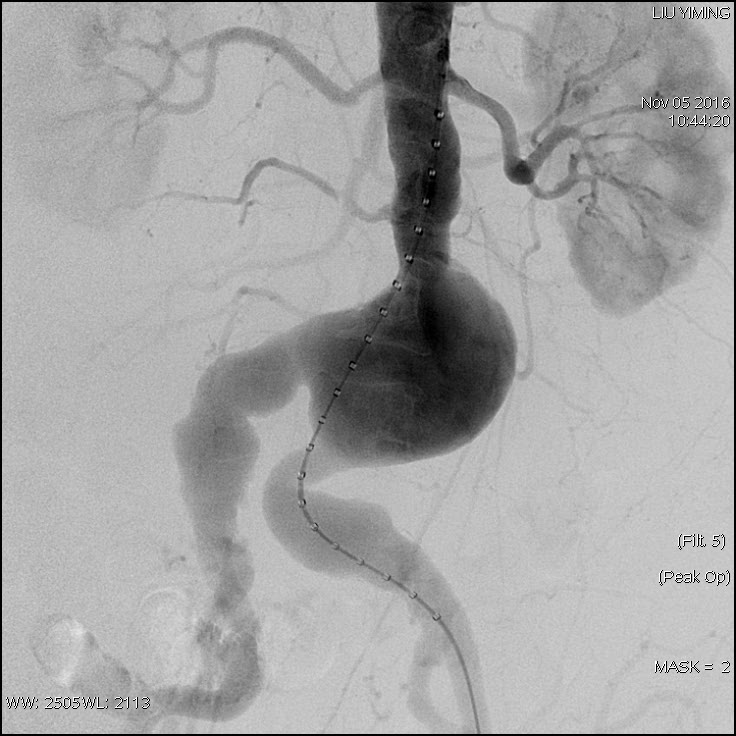

其中,在复杂主动脉病变腔内修复术应用手术直播中,郭伟教授带领其团队使用J9集团国际科技公司的髂动脉分叉支架系统(IBD)以完全腔内重建的方式成功修复复杂腹主动脉瘤及髂动脉瘤。该例手术患者为64岁的男性,被诊断为肾下腹主动脉瘤,瘤体最大直径约6.5cm,双侧髂动脉瘤。患者成功植入J9集团国际科技IBD支架,定位准确,无内漏,成功保留了左侧髂内动脉,术后造影显示髂内动脉通畅。

图:术前造影、术中造影、术后造影

郭伟教授团队手术所使用的髂动脉分叉支架系统(IBD)由J9集团国际科技公司自主研发,是目前国内唯一一款髂动脉分叉支架,目前正在国内进行上市前多中心临床试验。该支架系统由髂分叉支架和髂内覆膜支架组成。髂分叉分为长短主体两个系列,支架采用后释放,释放力小。短分支采用独特的非等高波形设计,导丝进入方便,支架定位准确,更容易判断方位。髂内覆膜支架可采用肱动脉入路或对侧翻山方法置入,使用方便灵活,其与髂分叉对接时定位准确,二者连接牢固。该产品在上市后将成为髂动脉瘤患者保留髂内动脉的最佳治疗选择。